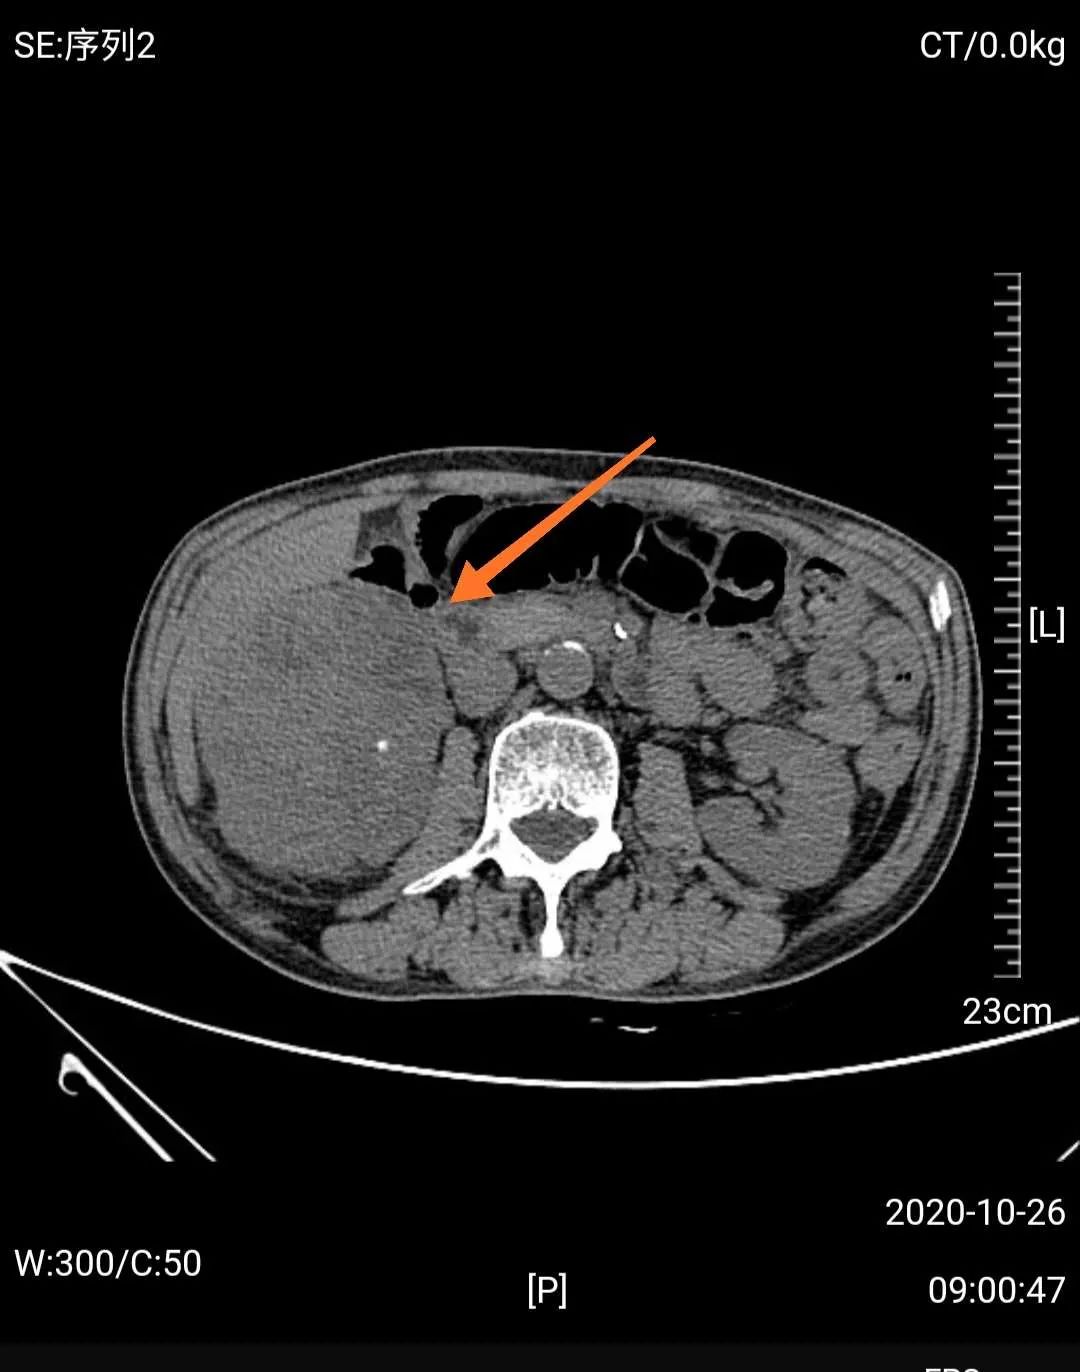

然而,门诊泌尿系超声检查发现,梁爷爷除了前列腺增生外,还有一个可怕的问题——右肾巨大肿瘤,考虑右肾癌可能性大。

经MDT团队研究,影像学团队分析认为老人诊断右肾癌相对明确,手术治疗是首选方案;心血管及肺病科团队认为老人虽然年龄大,高血压病史,但血压控制较好,心肺功能评估认为手术风险属于轻度;肿瘤科认为患者手术指征很明确,目前一般情况好,预期寿命长,内科治疗效果不及外科手术;中医治疗可以在外科手术后辅助,不能仅靠中医治疗。泌尿外科团队认为患者诊断考虑右肾癌,且左肾功能正常,右肾肿瘤巨大,建议根治性手术切除,考虑老人年纪大,开放手术创伤大,出血多,建议采用3D腹腔镜微创治疗。

如前所说的血尿,是肾癌的常见症状,而当肾癌患者发现有肉眼血尿时,表示肿瘤已经侵入肾盏、肾盂了。随着肿瘤生长,会牵拉肾包膜,或者侵犯到邻近的腰肌和器官,此时会产生腰部的疼痛,一般呈钝痛或隐痛;肾内的血块通过输尿管还会引起肾绞痛。假如是比较大的肿瘤,还可以在患者腰部或腹部触摸到肿块。血尿、疼痛、肿块称为肾癌的“三联征”,但多数患者只会出现其中之一或两项,而这时肾癌都已经发展到较晚期了。